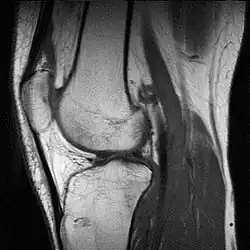

A grayscale MRI of a knee – different gray levels indicate different tissue types, requiring a trained eye.

A pseudocolor MRI of a knee created using three different grayscale scans – tissue types are easier to discern through pseudo color.